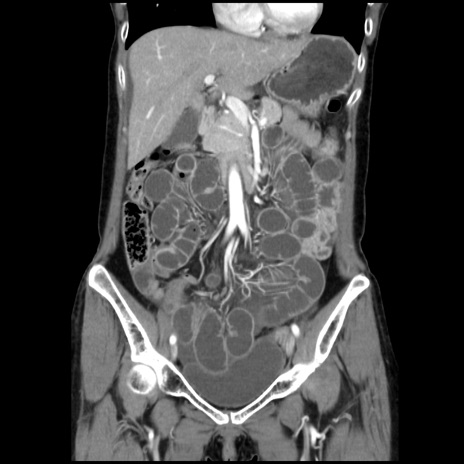

症例32(冠状断像)

【症例】40歳代 女性

【主訴】上腹部痛、嘔気・嘔吐

【現病歴】約9時間前頃から急に上腹部痛、嘔気、嘔吐が出現。改善しないため救急要請。

【既往歴】子宮頚癌(広汎子宮全摘術、放射線療法)、腸閉塞

【身体所見】腹部:平坦、軟、腸雑音亢進、上腹部を中心に腹部全体に圧痛あり。

【データ】WBC 8400、CRP 0.03